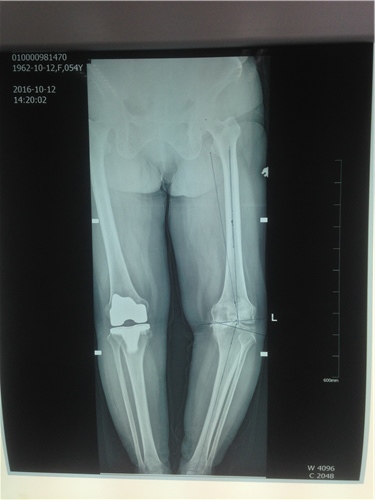

患者曾在2015年因右膝关节重度骨性关节炎,在西安行右全膝关节置换术。住入我院后,骨二科副主任医师胡洪波为患者做了详细全面的检查,最终诊断为左膝关节骨性关节炎IV期,右全膝关节置换术后,高血压病3级。因为患者左膝关节的疼痛,导致走路不稳,影响到了日常生活,已经达到了手术指征,骨二科医师在经过和患者及家属的反复沟通后,决定为患者实施左侧全膝关节表面置换术。

10月15日,由胡洪波主刀,为患者施左膝关节骨性关节炎全膝关节表面置换术,手术过程顺利。术后2天患者开始屈膝运动训练及肌力训练,3天即可扶支柱下床行走,术后7天出院,术中患者的膝关节畸形也成功纠正,目前患者膝关节功能良好,行动无阻碍。